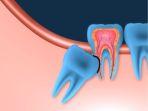

Salah satu solusi untuk mengatasi impaksi gigi bungsu adalah dengan dilakukan operasi pencabutan gigi bungsu.

Ada beberapa metode penanganan yang dapat dilakukan untuk menangani impaksi pada gigi bungsu.